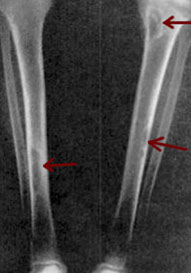

Ewing's sarcoma / PNET tumors

Anaplastic, high-grade malignant small round blue cell tumor MC in boys <15 yo

- may present as warmth and swelling in the diaphysis of long bones and in pelvis, scapula and ribs (bone involvement assoc c soft-tissue extension, can occur in any bone)

Imaging: "onion skin" appearance, saucerization (concave pressure erosion of the cortex when mass stuck bwt periostium and cortex), and Codman's triangle

*** Going out for wings and onion rings***

Ewing's sarcoma / PNET